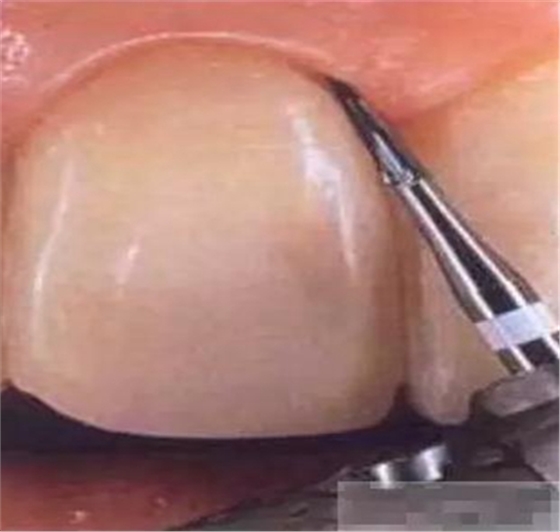

【基牙預(yù)備】樹脂貼面平齊牙齦邊緣是最佳設(shè)計(jì),或者使用齦上邊緣。

樹脂貼面平齊牙齦邊緣是最佳設(shè)計(jì),或者使用齦上邊緣

制備量問題:1-2種顏色,需要0.3mm牙體預(yù)備

3-5種顏色,需要0.5mm牙體預(yù)備 5種以上的顏色,需要0.7-1.0mm牙體預(yù)備

釉質(zhì)邊緣要用橡皮輪拋光

拋光可以去除懸釉。這樣經(jīng)過車針打磨過的釉質(zhì)表面會(huì)更加均一,形成良好的邊緣封閉。